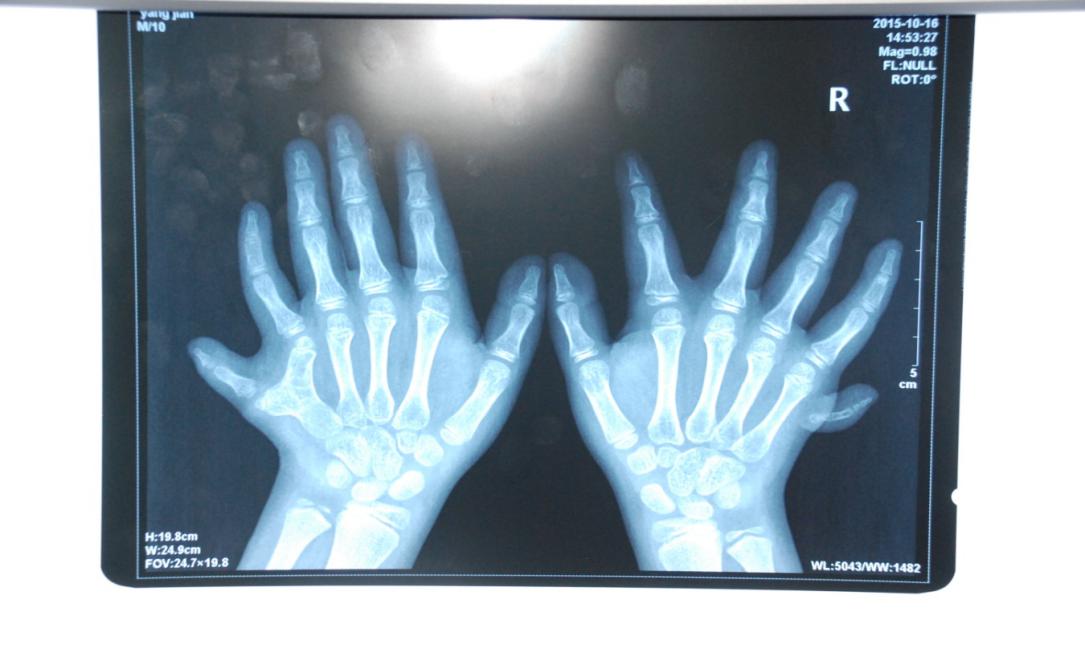

廈門眼科中心小兒眼科修陽暉博士在日常的診療過程中就接診了不少這樣的的特殊家庭,讓其尤為印象深刻的就是一年前接診的BBS綜合征患者。當(dāng)時(shí)來院就診的是一對親兄弟,之前已在多家醫(yī)院做過檢查,因其均有較大散光和斜視,肉眼下眼底檢查未見異常,故外院均診斷為弱視,這也符合眼科門診常規(guī)的診斷邏輯與思維。但由于兄弟倆均有智力發(fā)育遲緩、特殊面容及四肢均有六指和六趾的特異體征引起了修陽暉博士的警覺:會不會是一種特殊遺傳性疾病或綜合征?后續(xù)的檢查結(jié)果進(jìn)一步證實(shí)了修陽暉博士的懷疑---患兒均有夜盲,ERG、VEP及OCT檢查顯示雙眼的視網(wǎng)膜神經(jīng)上皮層結(jié)構(gòu)及功能均明顯異常。由于之前未遇到此種病例,修陽暉博士在診斷一欄寫下視網(wǎng)膜色素變性并打上了個(gè)問號,同時(shí)留下了病人的聯(lián)系方式。

BBS綜合征(Bardet-Biedl綜合征)是一種主要累及纖毛結(jié)構(gòu)與功能的罕見常染色體隱性遺傳性疾病。纖毛分布于哺乳動(dòng)物體內(nèi)的大多數(shù)細(xì)胞,它是一種廣泛存在于各種細(xì)胞表面的細(xì)胞器,體型微小但結(jié)構(gòu)復(fù)雜、作用強(qiáng)大,能感知細(xì)胞外機(jī)械和化學(xué)信號變化并協(xié)助其轉(zhuǎn)導(dǎo)到細(xì)胞內(nèi)部從而引起細(xì)胞應(yīng)答。高等動(dòng)物的視覺、觸覺、嗅覺、聽覺的傳遞都依賴于體內(nèi)外正常的纖毛結(jié)構(gòu)和功能。因此BBS綜合征常累及全身多個(gè)系統(tǒng)和器官,在臨床上主要表現(xiàn)為:視網(wǎng)膜色素變性、智力發(fā)育異常、向心性肥胖、多指(趾)、性腺發(fā)育異常、腎臟異常。除此之外還有許多諸如:語言發(fā)育障礙、聽力異常、嗅覺異常、斜視、白內(nèi)障、散光、牙齒發(fā)育異常、短指(趾)、并指(趾)、肝纖維化、糖尿病、高血壓等表現(xiàn)。